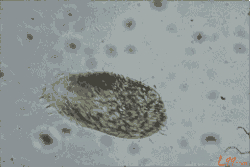

“食脑虫”通常指阿米巴原虫,它不是我们熟知的那种虫子,而是一类单细胞生物。

福氏耐格里阿米巴:一旦冲进鼻腔,可沿着嗅神经钻进大脑,引发急性阿米巴脑膜炎,进展飞快;